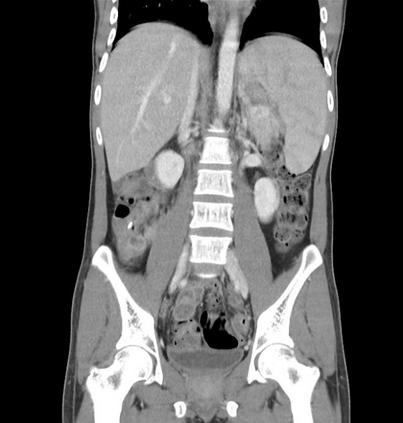

In this study, we aim to initiate the development of Radiology Foundation Model, termed as RadFM.We consider the construction of foundational models from the perspectives of data, model design, and evaluation thoroughly. Our contribution can be concluded as follows: (i), we construct a large-scale Medical Multi-modal Dataset, MedMD, consisting of 16M 2D and 3D medical scans. To the best of our knowledge, this is the first multi-modal dataset containing 3D medical scans. (ii), We propose an architecture that enables visually conditioned generative pre-training, allowing for the integration of text input interleaved with 2D or 3D medical scans to generate response for diverse radiologic tasks. The model was initially pre-trained on MedMD and subsequently domain-specific fine-tuned on RadMD, a radiologic cleaned version of MedMD, containing 3M radiologic visual-language pairs. (iii), we propose a new evaluation benchmark that comprises five tasks, aiming to comprehensively assess the capability of foundation models in handling practical clinical problems. Our experimental results confirm that RadFM significantly outperforms existing multi-modal foundation models. The codes, data, and model checkpoint will all be made publicly available to promote further research and development in the field.